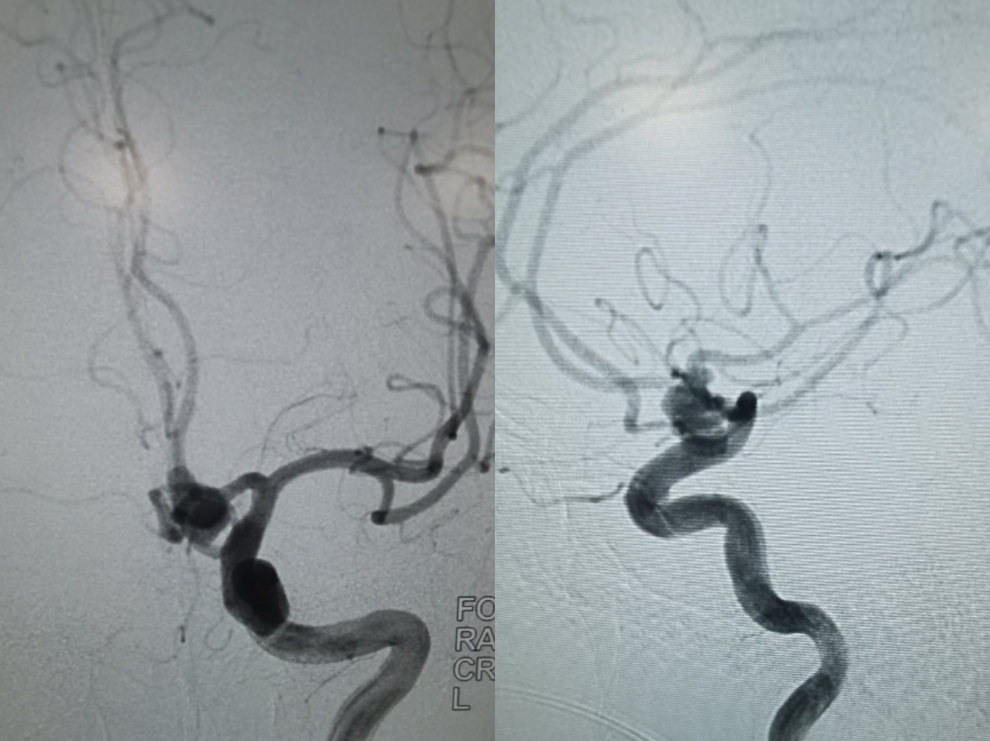

工作角度造影可以看到动脉瘤瘤体展示比较清楚,左侧A1全程清晰可见,隐约可以看到双侧A2的开口

采用双微导管技术,其中一根为导管头端塑成S形,指向瘤体的上部,另外一根微导管塑成C形,指向瘤体的下端,同时,两根味道管经过留颈部,可以起到对瘤颈以及双侧A2的部分保护作用。弹簧圈填塞过程中应反复造影,确保双测A2血流通畅。

术后三维旋转造影可以看到动脉瘤不显影,双侧A2血流通畅,达到预期手术效果。